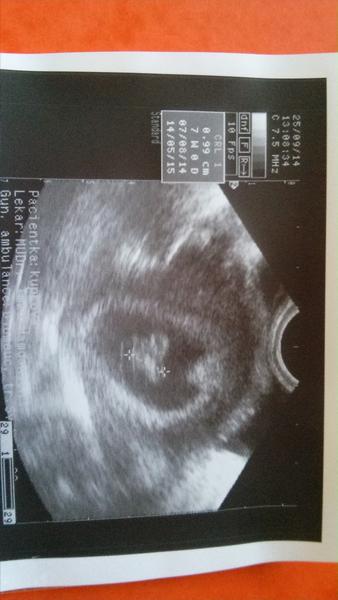

byli 1,3 cm velci.....8 týden, stále nemůžu pochopit, proč mi to nemohlo vyjít....

@bibianca taky to nechápu. Byla jsem 17.9, plod měl 3 milimetry. Teď za deset dnů tak pěkně vyrostl. A teď toto. Jenže kam by se schovalo, když tam bylo mimi tak pěkně vidět. Holky, to je hrozné. Proc, proc. To je nejhorší rána z celého IVF. Já už nevěřím že se dočkám. Chytlo se na pátý pokus a takový konec, už asi nemám sílu jít do dalších pokusu. Už nemuzu.